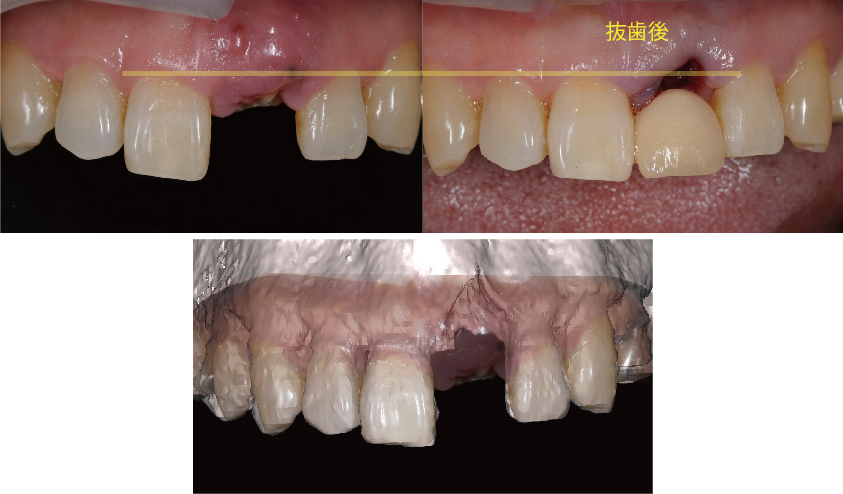

前歯のインプラント治療

前歯は周囲の骨が非常に薄いので抜歯後、時間の経過と共に歯茎は痩せて、骨も吸収して溶けてしまうことが多くあります

前歯のインプラント治療でとても重要なポイントは失った歯を回復してしっかり噛めるように機能を回復させることと、見た目が自然で人工物とわからないぐらいに綺麗にインプラント治療によって審美性を回復させることです。

しかし多くの場合、前歯の周囲の骨は非常に薄く、歯を失ったことになり顎の骨は吸収して痩せていき、それに伴って歯茎も下がってしまいます。

このままの状態でインプラント治療を行うと周りの歯と長さの違う不自然な被せ物(人工歯)になってしまい見栄えが悪く清掃性もよくありません。

新プラントプロで3次元的に分析を行い、インプラントを埋入する位置を決定し、サージガイドを作成します

そのため前歯のインプラント治療では、より正確な位置にインプラントを埋入することが求められ、インプラント周りの歯茎も自然な仕上がりになるようにインプラント周囲組織の骨や歯茎も回復をしてあげる必要があります。

コンピューターガイデッドインプラント治療 + 歯科用顕微鏡を用いたマイクロサージェリー 審美的に良好な結果が得られています

当院では、コンピューターガイデッド インプラント治療で正確な位置にインプラント手術を行い、そして前歯などの審美領域では顕微鏡を使用したマイクロサージェリー(顕微鏡下手術)を行うことで傷跡の目立ちにくい自然な仕上がりのインプラント治療を行っています。